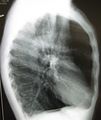

الپاثولوجيا العيانية للرئة تظهر انتفاخ الرئة المركزي بسبب التدخين.

قد يفيد تصوير الصدر بالأشعة السينية والعد الدموي الشامل في استبعاد أسباب أخرى في وقت التشخيص.[52] والسمات المميزة للأشعة السينية هي التمدد الشديد للرئتين، وانبساط الحجاب الحاجز، وزيادة حيز الهواء خلف القص، والأمراض الجلدية، في حين أنها قد تساعد في استبعاد أمراض الرئة الأخرى مثل ذات الرئة ووذمة الرئة أو الاسترواح الصدري.[53] يمكن لصورة الصدر عالية الوضوح باستخدام التصوير المقطعي المحوسب بالأشعة السينية أن تبين توزيع النفاخ الرئوي في جميع أنحاء الرئتين ويمكن أيضاً أن تكون مفيدة في استبعاد أمراض الرئة الأخرى.[11] إذا لم يكن مخططاً لإجراء عملية جراحية، فهذا نادراً ما يؤثر على العلاج.[11] ويتم استخدام غازات الدم الشرياني لتحديد مدى الحاجة إلى الأكسجين؛ ويوصى به لمن يُتوقع أن يكون حجم الزفير القسري لديهم1 أقل من 35%، والذين لديهم تشبع أكسجين محيطي أقل من 92% والذين تظهر لديهم أعراض قصور القلب الاحتقاني.[10] في مناطق العالم التي يشيع فيها نقص مضاد التريبسين ألفا-1، يجب أن يوضع في الاعتبار اختبار الأشخاص المصابين بمرض الانسداد الرئوي المزمن (خاصة من هم دون سن 45 ولديهم نفاخ رئوي يؤثر على الأجزاء السفلية من الرئتين).[10]